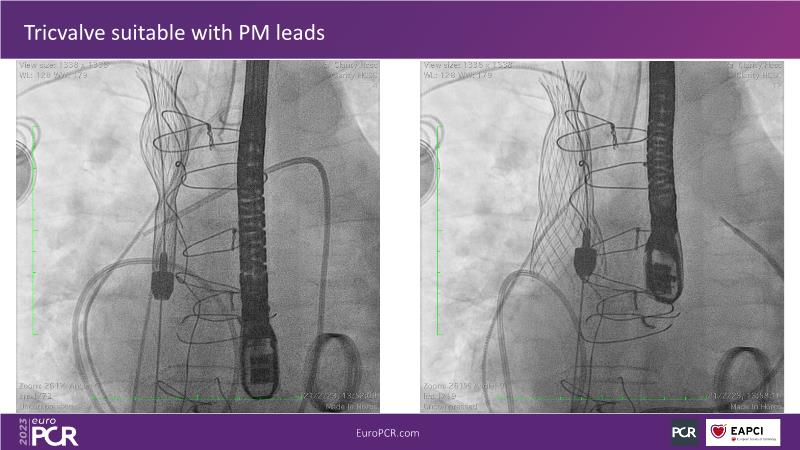

Discover the comprehensive guide to heterotopic valve replacement for patients experiencing right heart failure and tricuspid regurgitation. Join this session to gain insights into patient selection criteria, delve into the concept behind this innovative procedure, and grasp the fundamental aspects of its execution.

- To understand the concept behind

- To understand the basics of the procedure